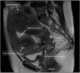

Direct invasion by extrinsic malignancy